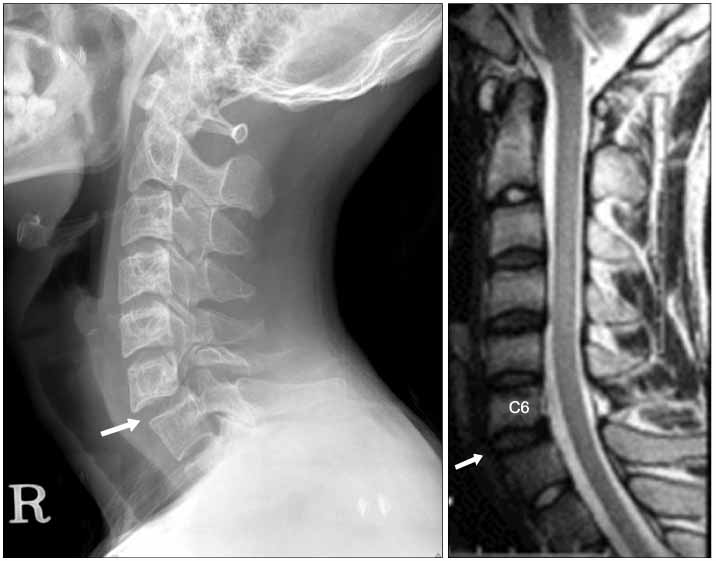

Для точного определения локализации проблемы и выявления возможных осложнений используются аппаратные методы исследования:

Рентгенография. При подозрении на смещение шейный отдел исследуется с помощью рентгенографии в различных проекциях. Если осложнений нет, спондилография выполняется в боковой и фронтальной проекциях. При наличии осложнений или выраженных симптомов смещения назначается рентгенография в косых проекциях. При подвывихе атланта диагностика осуществляется через рот.

Функциональные пробы. Этот метод также относится к рентгенографическим исследованиям. Снимки делают не в обычном положении головы, а при максимальном сгибании и разгибании шеи. Результаты рентгенографии в сочетании с функциональными пробами позволяют получить более полную картину смещения позвонков.

МРТ и КТ. Для детального изучения и диагностики сопутствующих заболеваний опорно-двигательного аппарата могут использоваться компьютерная и магнитно-резонансная томография.

Как распознать подвывих на рентгеновских снимках:

- высота межпозвоночного диска отличается от нормы;

- наблюдается смещение суставов относительно друг друга;

- при подвывихе атланта — ассиметричное расположение смещенной кости относительно осевого позвонка.